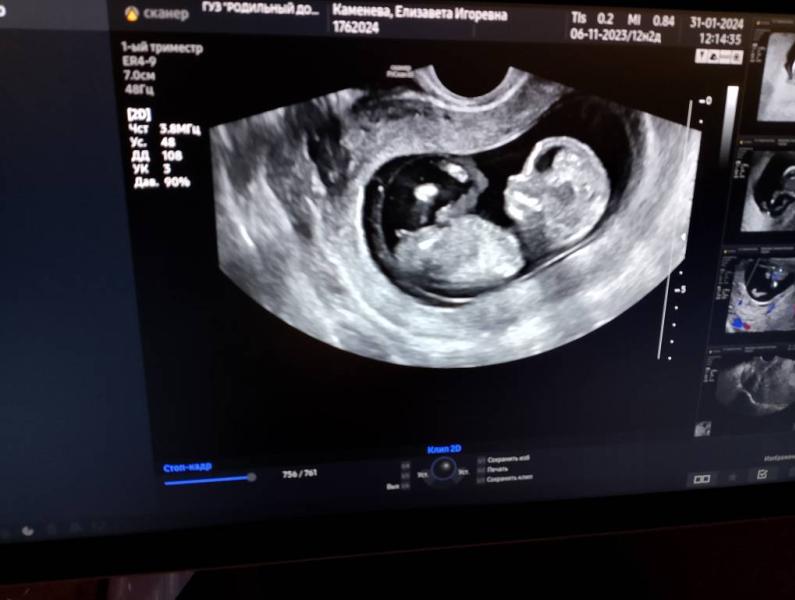

Всем доброго вечера сегодня был 1-й скрининг у моего воспаления о котором думала я когда показал тест полоску поизрак😂🥰

@felogena01 так на УЗИ ставят 13 недель ровно по акушерским

@felogena01 врач сказал если верх поднят половой орган это мальчик вниз это девочка

@felogena01 честно сама не знала о том как различать девочку и мальчика по УЗИ спасибо врачу 😂